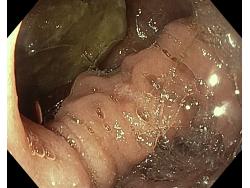

Uchyłki